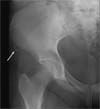

A 14-year-old girl came to the office with severe hip pain, which occurred after she attempted a cheerleading maneuver on a trampoline. She reported that she was bouncing as high as she could and landed on the trampoline with her left knee flexed and her right hip extended. On impact, she felt a "pop" that was immediately followed by right hip pain. She could barely move after the landing but managed to get off of the trampoline; she has been walking with pain since her injury.

The patient was taken to the local emergency department (ED) immediately after her injury, where she was told that her pain was caused by a severe muscle sprain. She was sent home with analgesics. Her mother later received a call from the emergency department physician who told her that a radiologist had viewed the x-ray films and had diagnosed an avulsion fracture (Figures). The ED physician recommended a bone scan to rule out decreased bone mineral density "because young girls should not get hip fractures."

Fractures of the extremities occur frequently, but involvement of the trunk and pelvis-as in the case of this patient-is uncommon. An avulsion fracture of the pelvis occurs when a muscle contracts very forcefully, pulling off a piece of bone where the muscle and tendon connect. This fracture seldom occurs in children younger than 12 years but is particularly common in teenaged athletes.3 Groin injuries occur in 5% to 9% of high school athletes from a sudden acceleration-deceleration or directional change during sporting events.3

The treatment of trampoline mishaps is injury-specific. In our patient's case, an orthopedic consultation was obtained. The orthopedist agreed with the diagnosis of avulsion fracture based on the radiographic findings and did not recommend a bone scan. Rest and symptomatic relief were prescribed, and the fracture was allowed to heal.